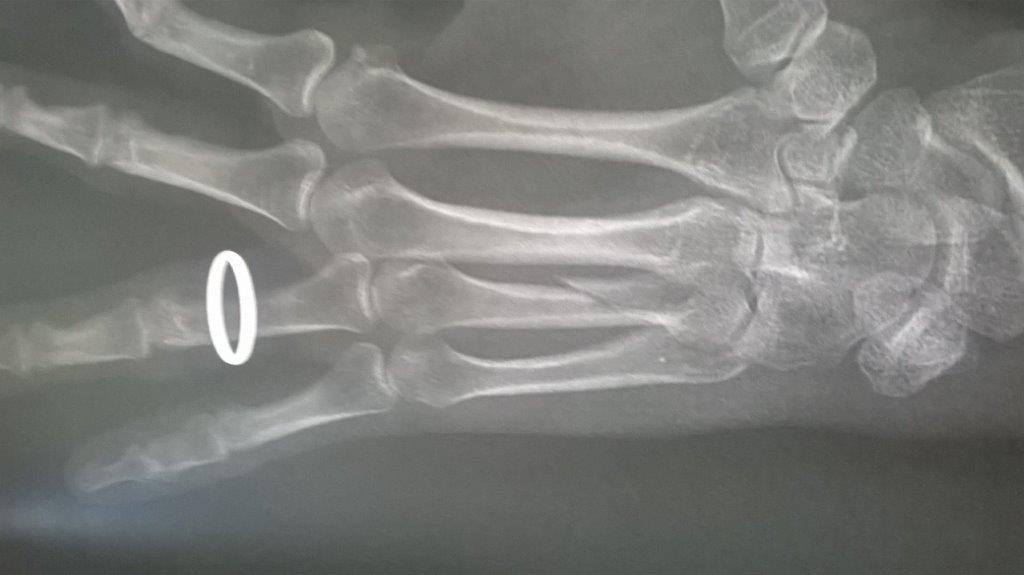

Résultat : fracture de la main gauche

Fichier(s) joint(s):

WP_20170914_001.jpg [ 47.5 Kio | Vu 29225 fois ]

Mais je confirme que ma saison de triathlon s'achève aujourd'hui. Main gauche immobilisé. Je suis au regret de déclarer forfait pour Paladru et d'abandonner les Mixirilliettes à leur triste sort